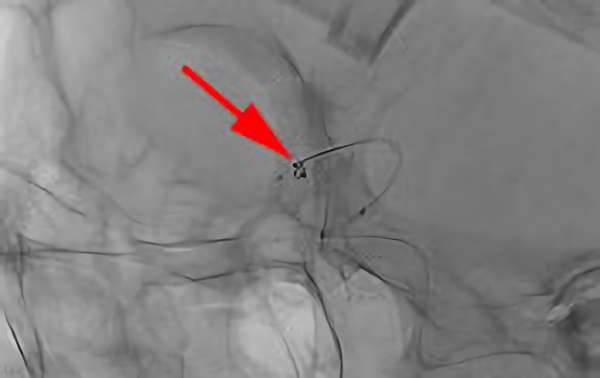

No.1628 手術中